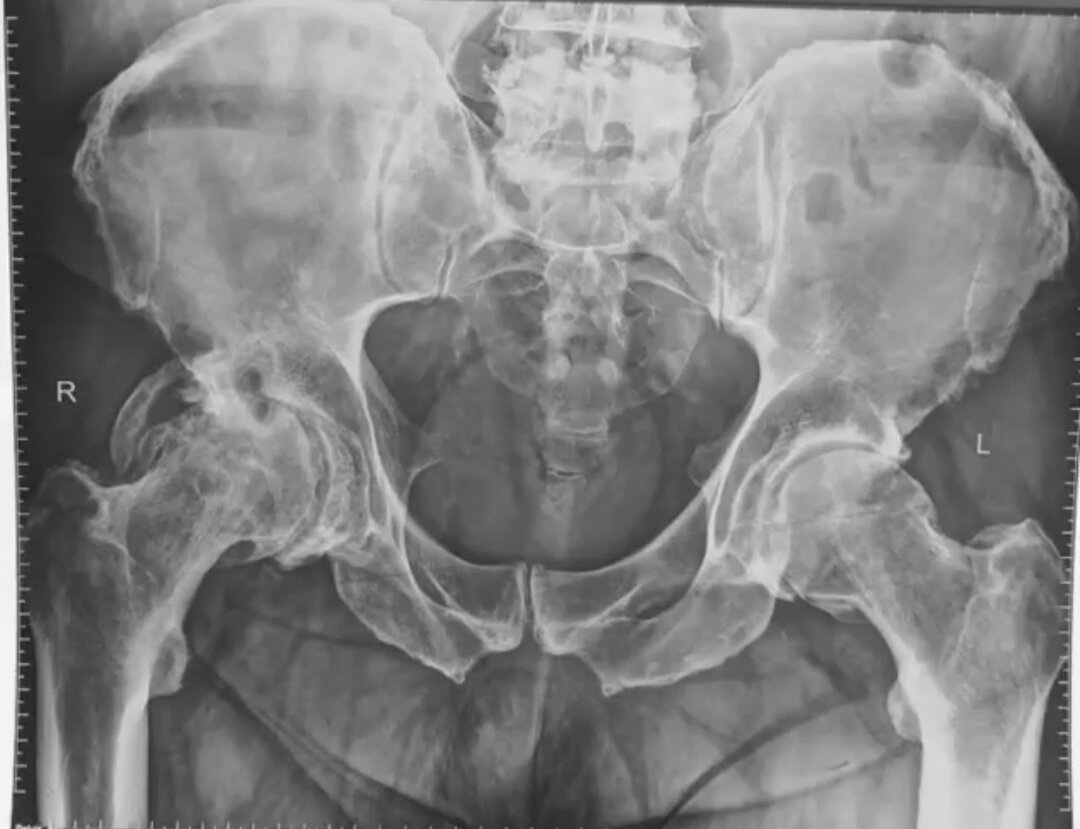

Коксартроз тазобедренного сустава - это состояние, при котором суставной хрящ, обеспечивающий гладкие скользящие движения поверхности сустава, постепенно изнашивается. Такой хрящ уже не скользит, а его поверхность похожа на наждачную бумагу. По мере того как истирается хрящ, в процесс вовлекаются кости (головка бедренной кости и вертлужная впадина). При длительном артрозе тазобедренного сустава в костях вследствие разрушения хряща образуются более плотные слои костной ткани (участки склероза). В норме, хрящ амортизирует нагрузку, но если хрящ истончен, то на кость приходится большая ударная нагрузка. Коксартроз проявляется болью, тугоподвижность и снижением амплитуды движений в суставе. На ранних стадиях коксартроза боль и скованность проявляется после сна или длительного сидения и проходят через несколько минут. На самых тяжелых стадиях коксартроза боль становится постоянной и не проходит даже ночью. Коксартроз тазобедренного сустава можно лечить консервативно (контроль массы тела, за

Коксартроз тазобедренного сустава - это состояние, при котором суставной хрящ, обеспечивающий гладкие скользящие движения поверхности сустава, постепенно изнашивается. Такой хрящ уже не скользит, а его поверхность похожа на наждачную бумагу.

По мере того как истирается хрящ, в процесс вовлекаются кости (головка бедренной кости и вертлужная впадина). При длительном артрозе тазобедренного сустава в костях вследствие разрушения хряща образуются более плотные слои костной ткани (участки склероза). В норме, хрящ амортизирует нагрузку, но если хрящ истончен, то на кость приходится большая ударная нагрузка.

Коксартроз проявляется болью, тугоподвижность и снижением амплитуды движений в суставе. На ранних стадиях коксартроза боль и скованность проявляется после сна или длительного сидения и проходят через несколько минут. На самых тяжелых стадиях коксартроза боль становится постоянной и не проходит даже ночью.